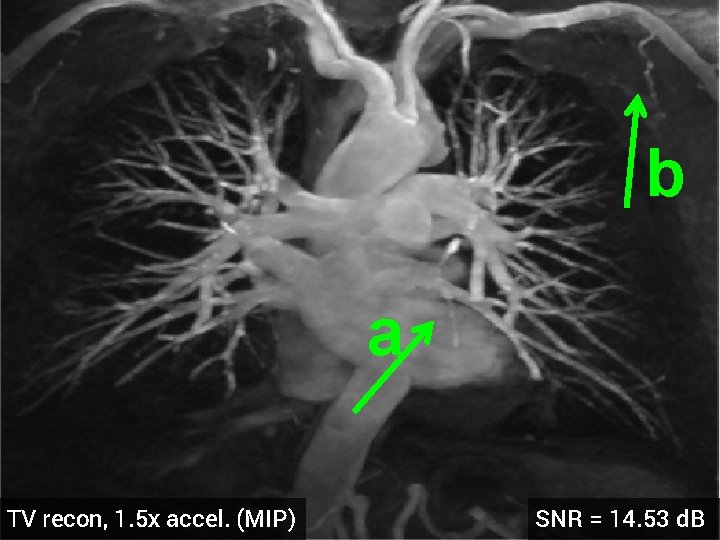

3 -D Compressed Sensing MRA § 512 x 76 voxel MRA dataset obtained from physiobank (see ref. [6]) § Simulated single coil acquisition § Retroactively undersampled at 1. 5 -fold acceleration § Random Gaussian sampling of k-space § 5 d. B additive Gaussian noise § Optimized regularization parameter MIP of original MRA dataset

b a TV recon, 1. 5 x accel. (MIP) SNR = 14. 53 d. B

b a HDTV 2 recon, 1. 5 x accel. (MIP) SNR = 15. 11 d. B

3 -D Quantitative Results Table 3: 3 -D Comparisons. SNR (in d. B) of recovered images with optimal reg. param. Denoising Cell 1 Cell 2 Deblurring Cell 1 CS-MRI Cell 2 Cell 3 Angio, acc=5 Angio, acc=1. 5 Cardiac TV 17. 12 16. 25 19. 02 16. 43 14. 50 13. 87 14. 53 18. 37 HDTV 2 17. 25 16. 70 19. 15 16. 60 14. 87 14. 23 15. 11 18. 56 HDTV 3 17. 68 17. 14 19. 73 17. 43 15. 23 14. 01 14. 70 18. 50 § HDTV outperforms TV in all experiments § HDTV 3 better for denoising and deblurring § HDTV 2 better for CS-MRI